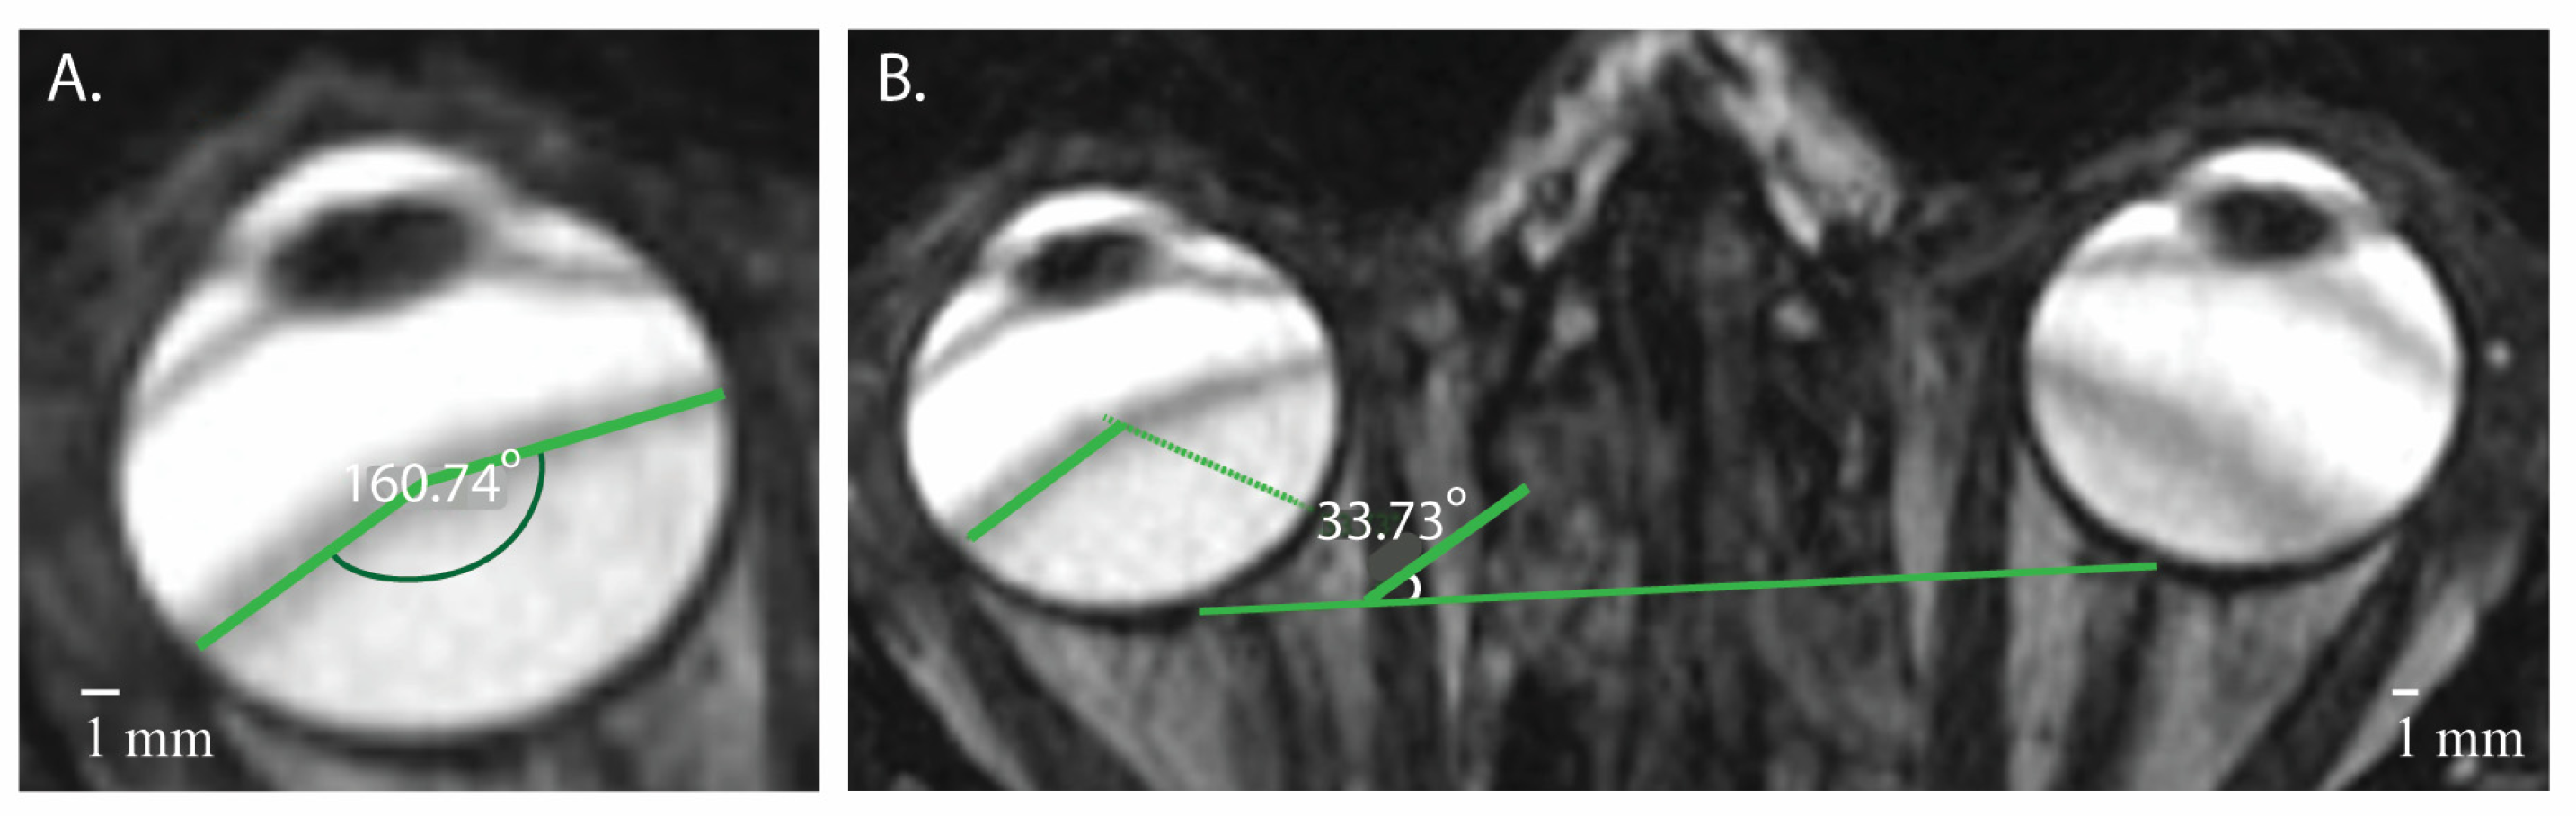

3.2. Signal Areas in the Eye

| Banding Artifacts of the Eye | |||

| Mean (SD) Number of Bands in the Eye (n) | Mean (SD) Internal Angle of the Banding Artifacts (°) | Mean (SD) Angle of Banding Artifacts in Relation to the Optic Nerve Plane (°) | |

| Right eye | * 1.47 (1.41) | * 142.60 (13.76) | 58.01 (24.66) |

| Left eye | * 1.27 (0.64) | * 148.10 (14.21) | 54.47 (24.46) |